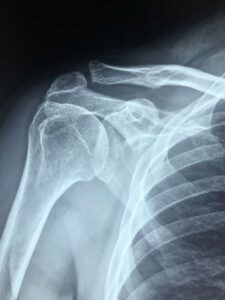

Bolestné po autonehodě může žádat především poškozený nezaviněnou autonehodou, ať se již jednalo o řidiče, chodce nebo spolujezdce. Bolestné představuje jednu z náhrad odškodnění za zranění při dopravní nehodě. Mimo bolestného lze obvykle u poškozeného žádat také odškodnění ušlého výdělku, nákladů léčení a cestovného. U vážnějších zranění také náhradu nákladů péče o nesoběstačného poškozeného a ztížení společenského uplatnění v případě trvalých zdravotních následků po autonehodě.

Bolestné po autonehodě v roce 2022 lze získat žádostí o odškodnění této náhrady u pojišťovny vozidla viníka nehody. Odškodnění bolestného se vypočte na základě lékařských zpráv poškozeného dle Metodiky Nejvyššího soudu k náhradě nemajetkové újmy na zdraví. Právo žádat odškodnění přímo u pojišťovny namísto viníka nehody vyplývá přímo ze zákona o pojištění odpovědnosti z provozu vozidla.

Při výpočtu odškodnění bolestného se vychází z bodového hodnocení každého zranění. Hodnota jednoho bodu je každý rok pohyblivá a odvozuje se od jednoho procenta průměrné hrubé mzdy za kalendářní rok předcházející roku, v němž vznikla bolest.